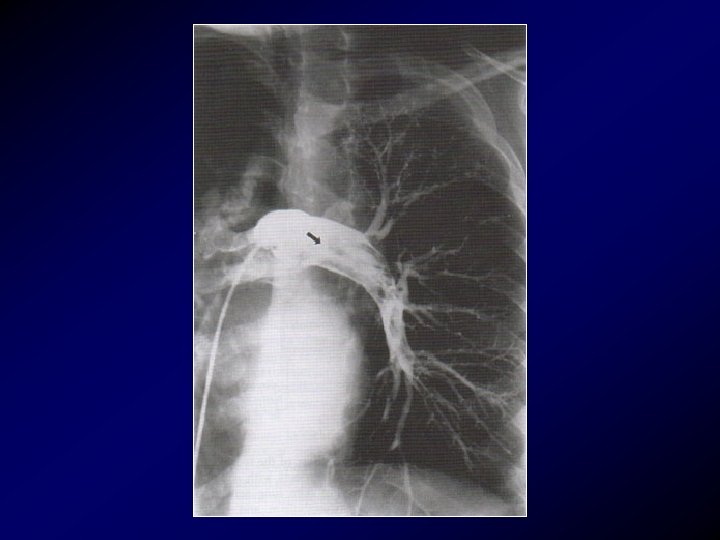

Angiografia

Angiografia • L’angiografia polmonare è una flebografia ascendente con mezzo di contrasto per lo studio della cava inferiore e della vascolarizzazione polmonare. E' il gold standard per la diagnosi di embolia polmonare. Le indicazioni riguardano: 1) pazienti con scintigrafia polmonare scarsamente diagnostica ma con quadro clinico altamente sospetto, 2) pazienti in cui sia indicato il trattamento trombolitico o l'embolectomia, 3) pazienti in cui sia necessario confermare la diagnosi per un notevole rischio emorragico legato all'impiego del trattamento anticoagulante per via sistemica.